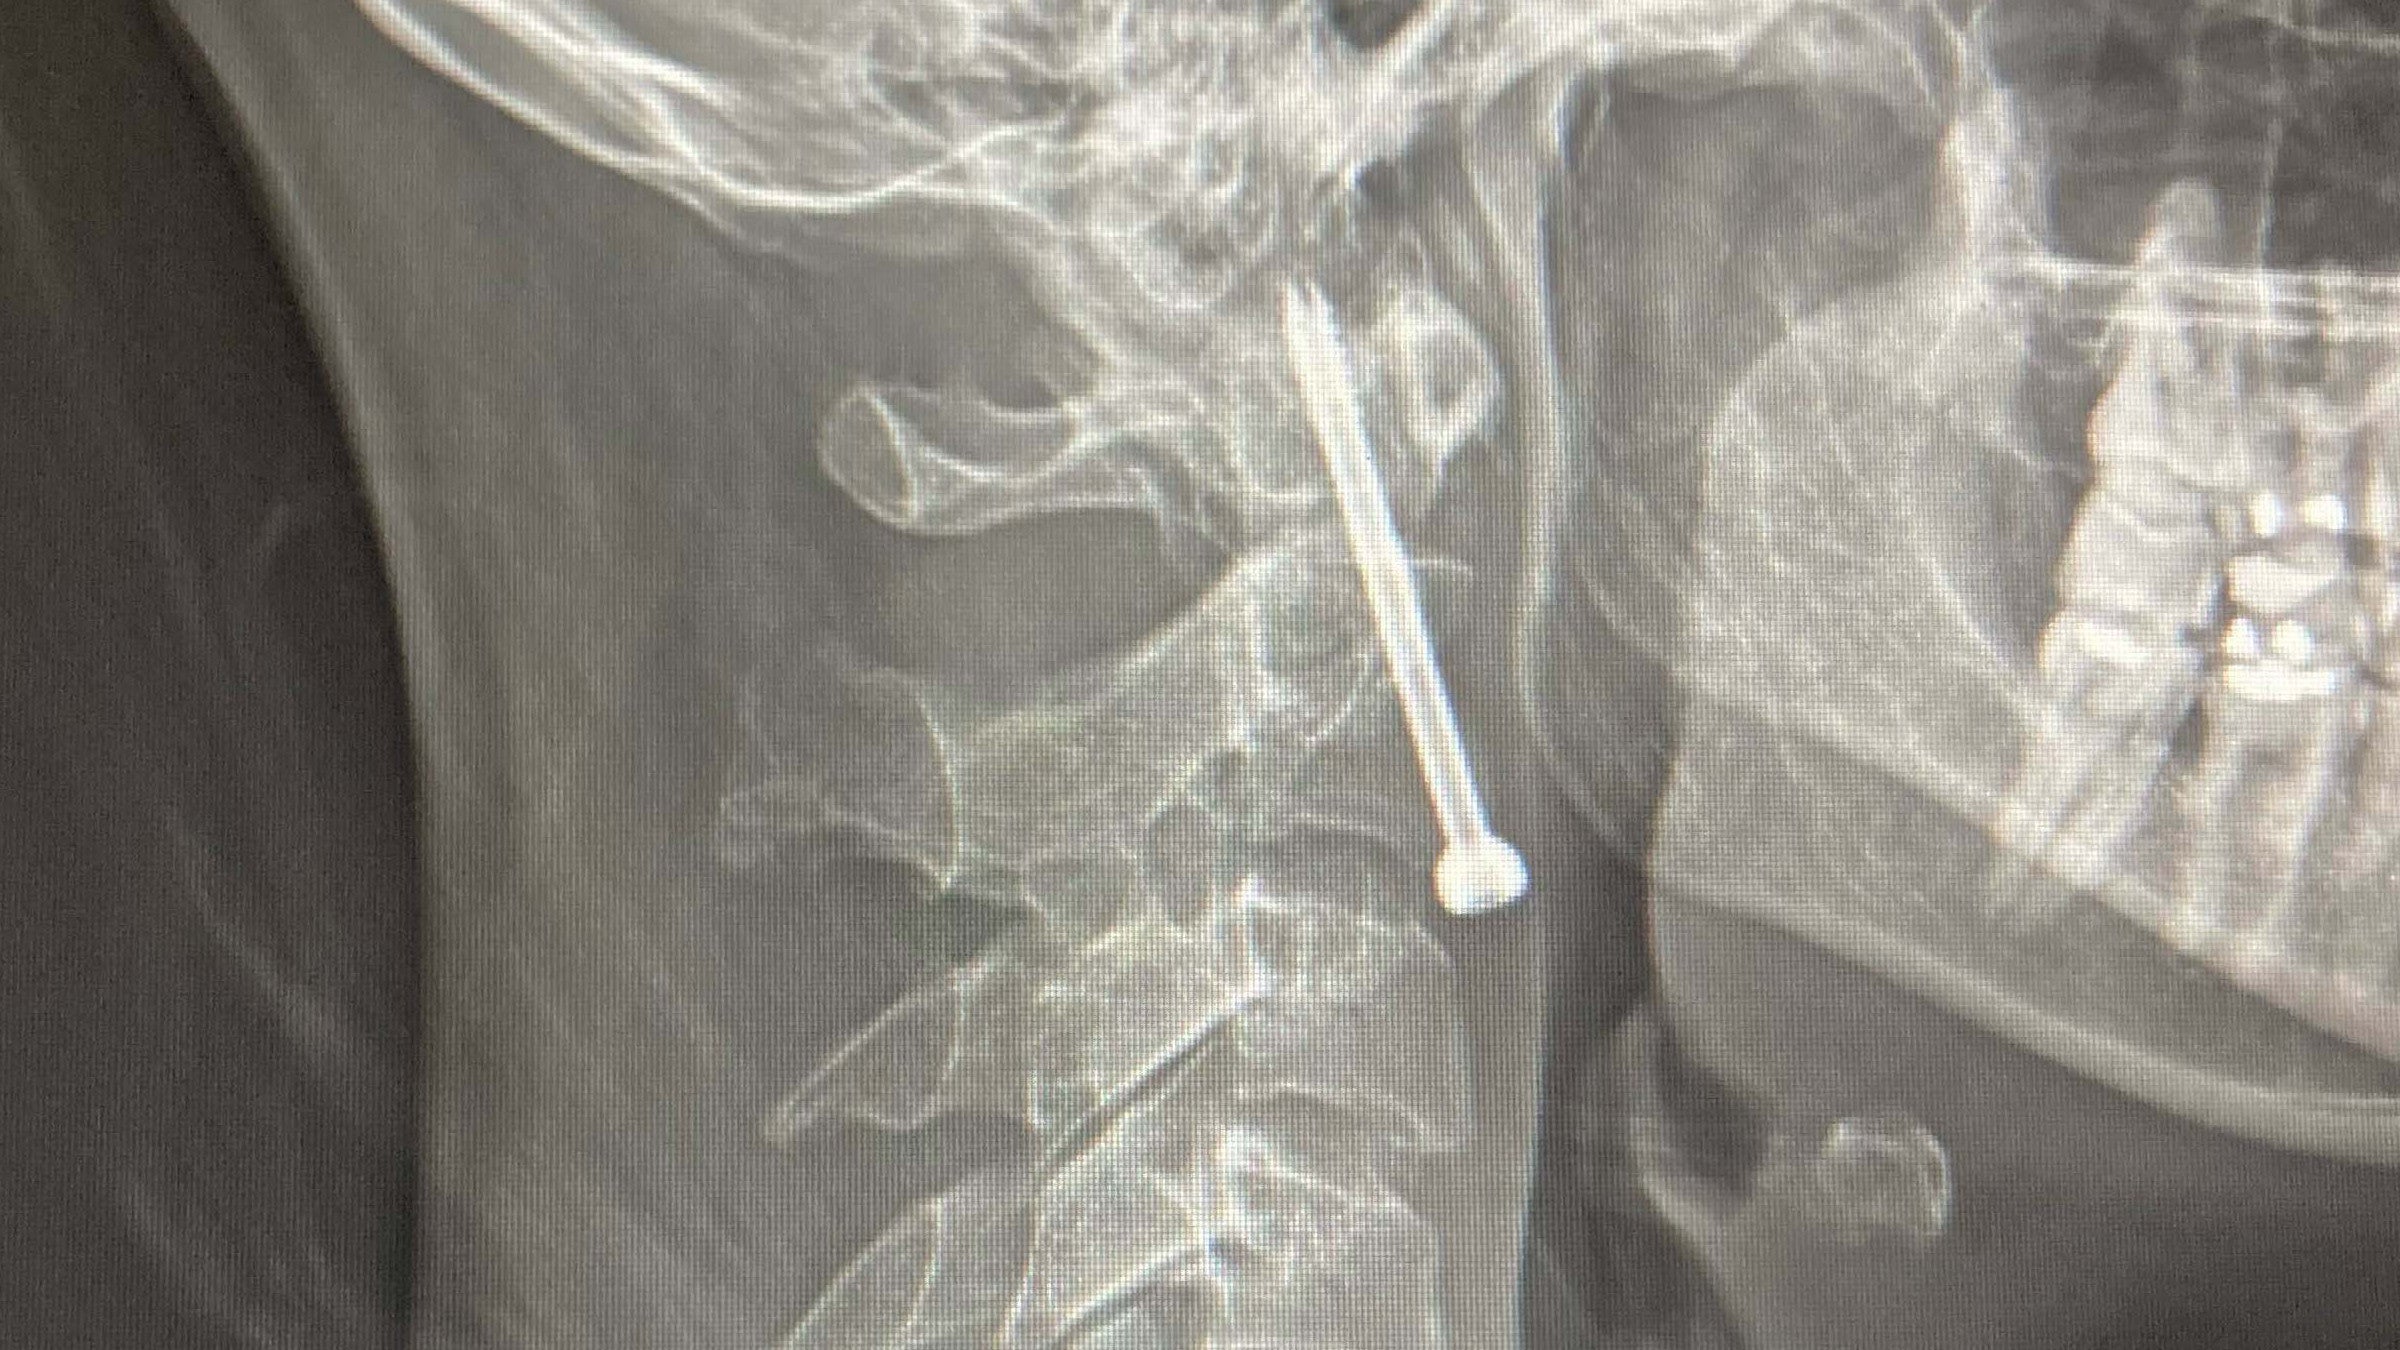

In the hospital, I learned that I’d cracked three vertebrae in my neck—and the pieces had already moved. I needed emergency surgery, but they couldn’t get me into the operating room for two more days. If my vertebrae shifted any more during that time, I might never walk again.